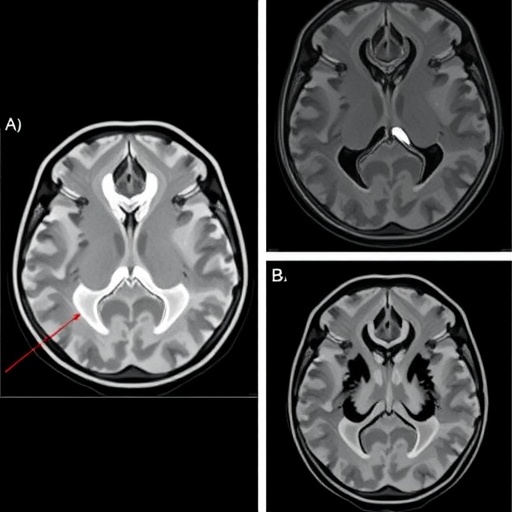

Traditional forensic age estimation methods usually rely on physical examinations, dental assessments, or analysis of hand-wrist radiographs. However, these approaches are often subject to variability due to ethnic differences, environmental conditions, and individual biological uniqueness. The innovative use of elbow MRI scans addresses some of these challenges by providing high-resolution images of ossification centers and cartilage that show characteristic developmental stages at different chronological ages. This imaging modality is non-invasive and free from radiation exposure, rendering it highly suitable for repeated forensic evaluation.

Another compelling aspect of this study is the comprehensive characterization of the ossification stages observable in MRI scans of the elbow joint. The investigation delineates specific morphological and structural markers corresponding to distinct developmental phases. Such detailed morphometric analyses empower forensic practitioners to anchor age estimations in objective anatomical landmarks rather than relying solely on subjective interpretation, a critical improvement in forensic evidence evaluation.

From a technical standpoint, the MRI protocols employed in this study prioritize sequences optimized for cartilage and bone visualization, ensuring that the key developmental indicators are clearly discernible. This meticulous imaging technique undergirds the subsequent data mining process, ensuring that input quality is maintained at the highest standard. The resultant data integrity amplifies the confidence levels associated with age classifications derived from this approach.